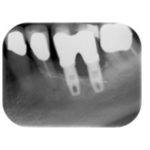

La malattia perimplantare: cause e fattori di rischio

Mucosite-perimplantare-2